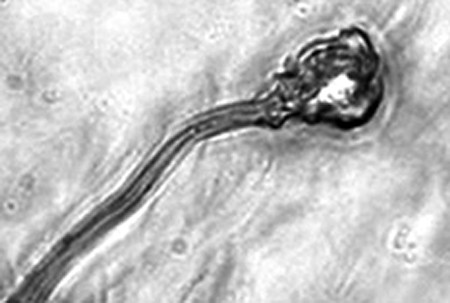

據(jù)報告的主要作者卡里姆教授介紹,這種試管培育精子(IVDsperm)與人類自然產(chǎn)生的精子并不完全一樣,但兩者擁有4個重要的相似點(diǎn):它們包含有23個染色體;有精子那樣的頭和尾巴;有可以使卵細(xì)胞受精的蛋白質(zhì);它們也可以像天然精子一樣游動。